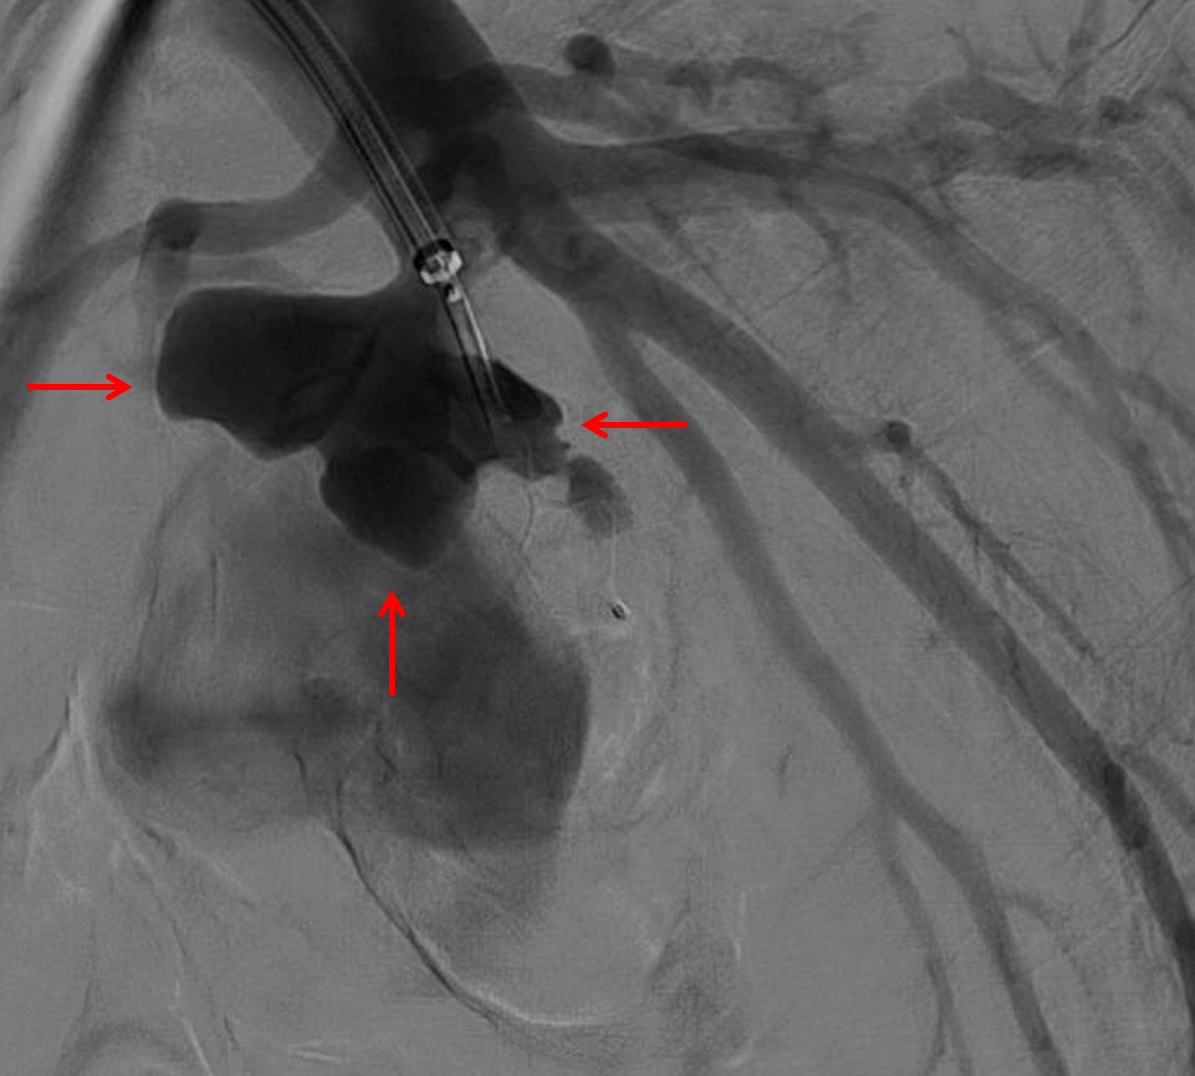

Sample ReportFindings concerning for necrotizing pneumonia in the left lower lobe with a large associated pulmonary arterial pseudoaneurysm. Recommend conventional pulmonary arteriogram and possible endovascular coiling.